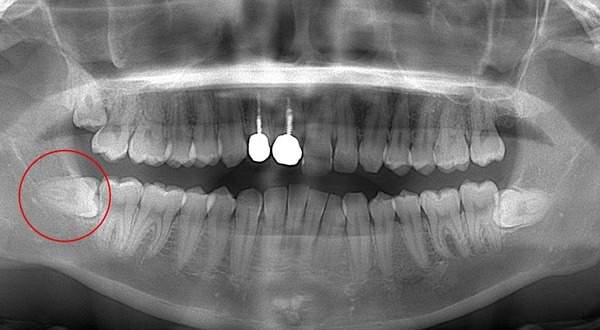

抜くと痛い親知らずとは

麻布十番歯科で親知らずが横向きに生えている症例のレントゲン写真のイメージ

親知らずを抜くのに痛みを伴いやすいものが写真とレントゲンにあるような真横にはえているもの、もしくは斜め下にはえている下顎の親知らずです。また、根が曲がっていたり、数が多いほど抜くのが難しい経口にあります。

この場合、歯ぐきを切ったり、歯を囲っている周りの骨を削って抜いていかなければなりません。

そのため、抜歯後は腫れや痛みが伴いやすくなります。 抜歯中は麻酔を行いますが、骨が硬い方は麻酔がなかなか効かないこともあります。そのため痛みを伴うことがあります。

また上顎でも根の数が多かったり曲がっていたり、または上顎洞といって、お鼻の横にある副鼻腔と交通しているような親知らずでは、痛みが伴うことがあります。